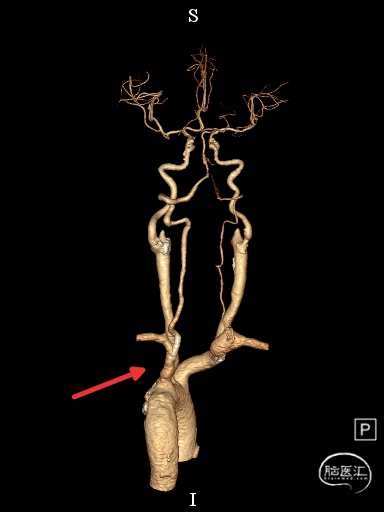

左侧椎动脉开口重度狭窄,前向血流缓慢,V4闭塞。

左侧椎动脉V4段闭塞、左侧椎动脉起始部重度狭窄、左侧小脑急性脑梗塞、右侧颈内动脉起始部狭窄。

左侧椎动脉急性闭塞,椎动脉起始部重度狭窄影响通路建立,后循环缺血再灌注损伤。

保留微导丝、Guiding回撤到锁骨下,观察椎动脉开口:椎动脉开口无法维持。拟行椎动脉开口支架成形术,选用4mm*15mm Bridge椎动脉雷帕霉素靶向洗脱支架。

取栓技术个体化:术中造影证实为左侧椎动脉闭塞,左侧椎动脉为后循环优势动脉,术后出血风险较高,合并椎动脉起始部重度狭窄可能需要治疗,因此选择NeuroHawk取栓支架,该支架显影性良好、费用较低、效果佳,血栓一次性完整取出,SWIM技术取栓一次后前向血流恢复,椎动脉开口单纯球扩后不能维持,考虑远期疗效,选用了Bridge椎动脉雷帕霉素靶向洗脱支架。